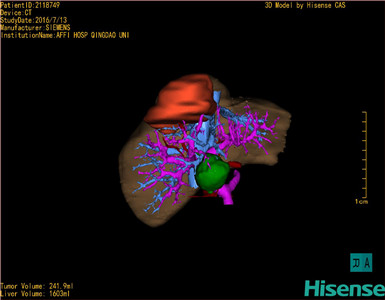

术前三维重建及手术方案设计:

将0.625mm双源薄层CT资料的静脉期和动脉期Dicom格式文件导入海信CAS系统。

通过调节窗宽窗位调整CT序号,对肿瘤,肝实质,胆囊,下腔静脉,肿瘤,肝动脉、门静脉及肝静脉等进行三维重建;系统自动计算肿瘤体积和肝脏体积。

模拟手术操作,自动计算切除肿瘤体积。肝脏体积为1603ml,肿瘤体积为241.9ml,肿瘤体积为肝脏体积的15.1%,通过比对70-80岁正常肝脏体积为1118.08±190.14ml,通过术前模拟手术,精准判断切除后剩余肝脏体积能耐受,避免肝衰竭发生。

术前手术方案的规划。

术前三维重建:

重建图片